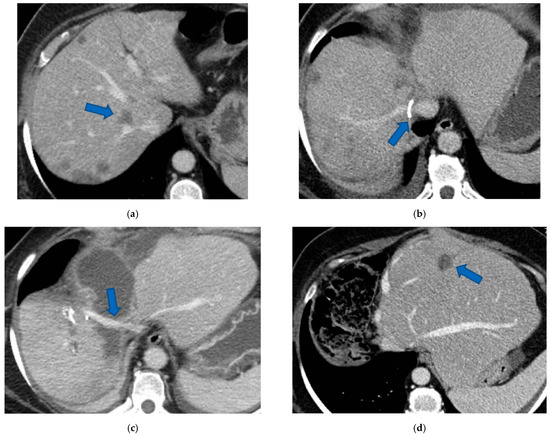

3.3. PS-TSH with SS-PVE

Figure 6. CT Images of PS-TSH with SS-PVE performed to treat 35 bilateral CRLMs. (a) Partial response after FOLFOXIRI + Bevacizumab 12 cycles; FLR (=S2/S3) volume is 15%. (b) Blue arrow points GP 5 after the first stage consisting of resection of S1/S4 extended to S2/S8/S5 plus metastasectomy of S2 with tangential resection of LHV. (c) Fourteen days after stage 1 SS-PVE was performed on the right liver preserving GP 5 (blue arrow); 37 days after SS-PVE FLR (=S2/S3/S5) increased up to 37%. (d) Blue arrow points GP 5. Twenty-five months after PS-TSH with SS-PVE the patient is disease free; the liver’s only disease recurrence was successfully treated with another 3 liver resections (2 on the right liver and 1 on the left). Abbreviations: PS-TSH: parenchyma-sparing TWO-STAGE hepatectomy; SS-PVE: super-selective portal vein embolization; CRLM: colorectal liver metastases; FLR: future liver remnant; S: segment; GP5: glissonean pedicle for segment 5; LHV: left hepatic vein.